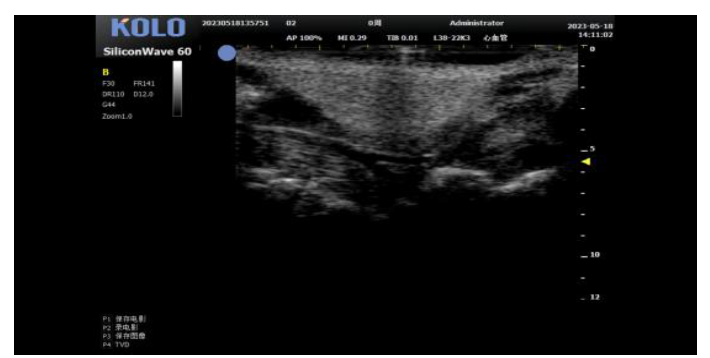

5肿瘤测量(肿瘤大小精确测量)